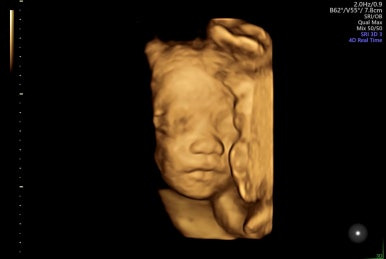

28주 1일

입체초음파로 태아의 얼굴을 볼 수 있는 시기이다!

제일 기다렸던 때이고, 다행히 태아 얼굴을 볼 수 있었다.

다음 초음파는 3주 뒤, 그 다음 9개월 차 부터는 2주 간격으로 검사한다고 한다.